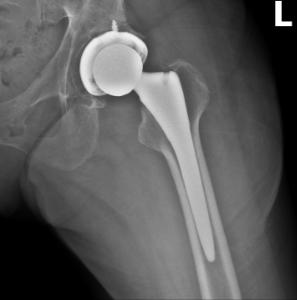

Left Hip 2

February 3, 2019